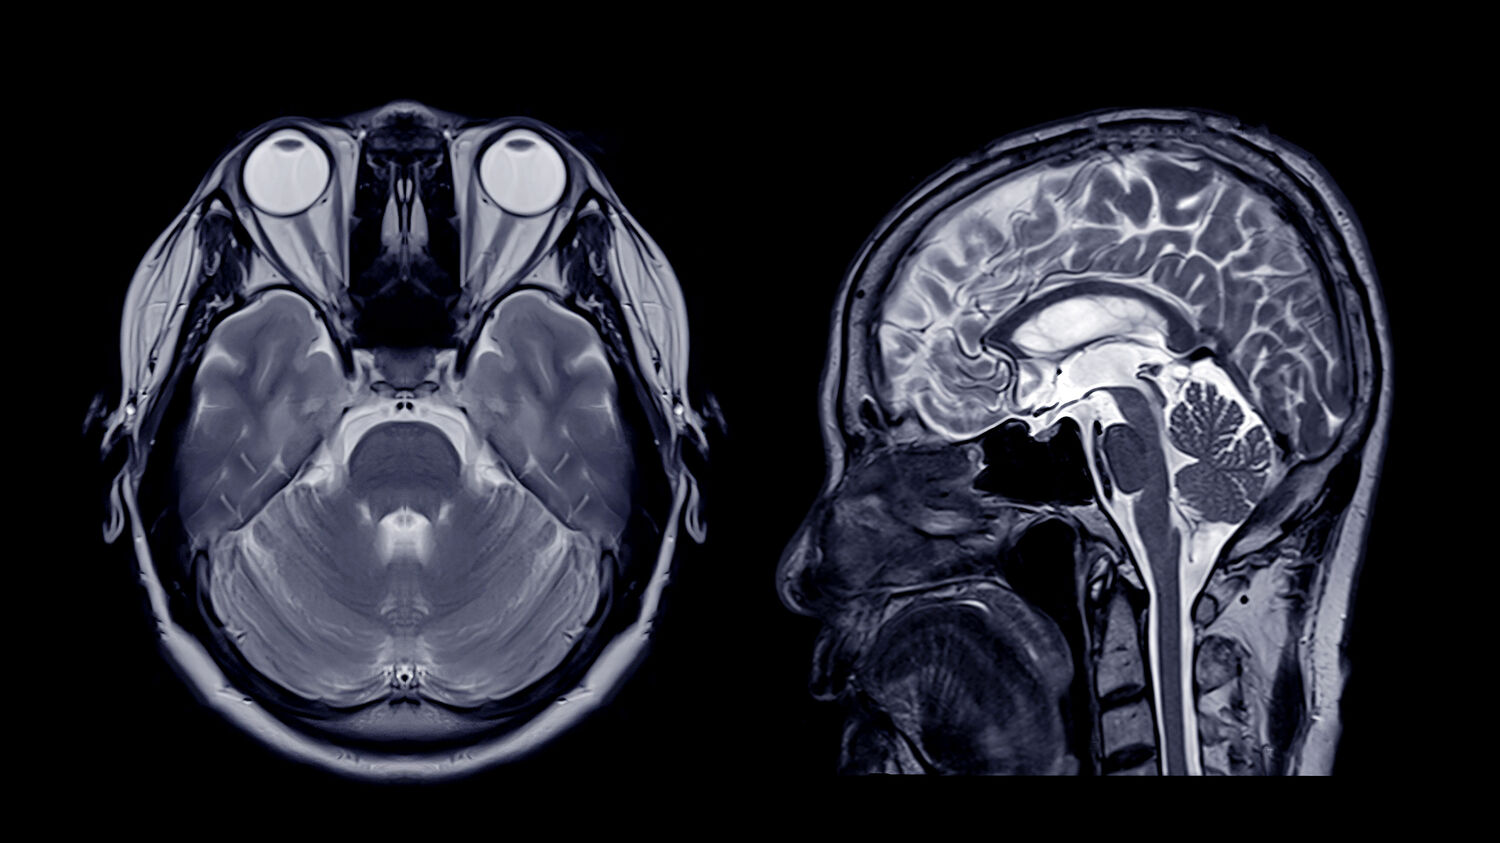

Die Magnetresonanztomographie, kurz MRT, ist ein bildgebendes Verfahren, das dabei unterstützt, Krankheiten festzustellen, sie auszuschließen sowie Krankheits- und Therapieverläufe zu kontrollieren. Eine Schädel-MRT eignet sich beispielsweise, um bei Schwindel, anhaltenden Kopfschmerzen oder Verletzungen des Schädels, eine Diagnose zu stellen.

Wie sind die Graustufen auf dem MRT-Bild zu deuten?

Das Gewebe stellt sich in den unterschiedlichen Sequenzen je nach Signal in verschiedenen Grautönen dar.

Die weißen Flecken, die man auf MRT-Bildern sieht, können viele Ursachen haben. Im Falle einer MRT vom Kopf können die weißen Punkte unter anderem als Liquor (Hirnwasser), Narbe oder Entzündung gedeutet werden.

Zur Struktur des Kopfes gehören viele verschiedene Bereiche. Neben dem Gehirn (inkl. Großhirn, Kleinhirn, Balken, Thalamus, Hypothalamus, Brücke, Medulla oblongata) gehören die Augen, Ober- und Unterkiefer, Nase und Nebenhöhlen, Innenohr, Mund und Rachenraum sowie Nerven und Hypophyse zum Kopf. Die MRT-Untersuchung findet demnach auch in verschiedenen medizinischen Einsatzgebieten Anwendung. Hier einige Beispiele: